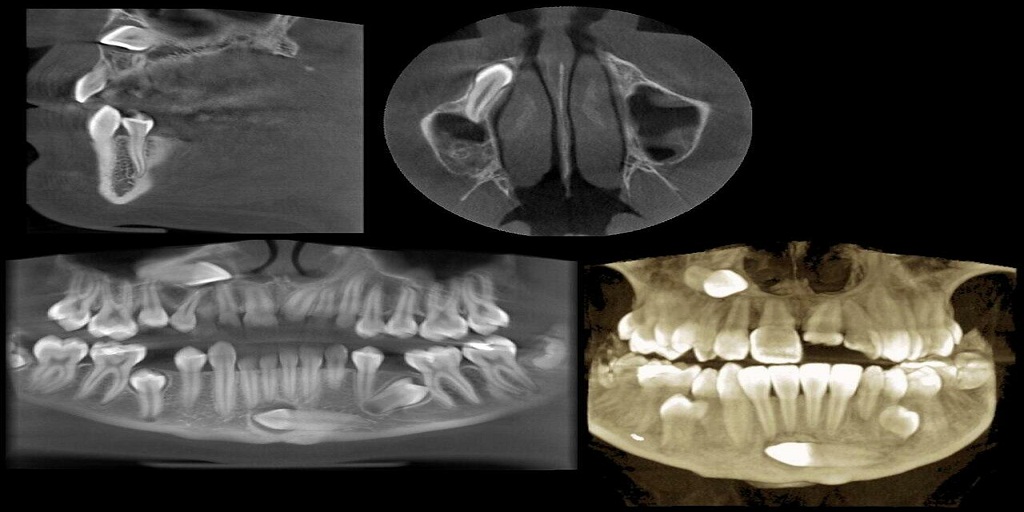

Romexis brings together all Planmeca equipment at a dental clinic, from CAD/CAM technology to imaging devices and dental units. Romexis 3D software can help you capture, store, access, manage and share dental cone beam images easily. The following features are only some of those that make Planmeca Romexis stand out from the competition.

Romexis software is an all-in-one solution for your dental imaging needs, offering storage and management of numerous types of 2D and 3D imaging. The following is a sample of their available software models:

● 2D Cephalometry (ceph analysis, surgical planning, and treatment follow-ups in 2D).

● 3D Cephalometry (ceph analysis using CBCT images).

● 3D Orthodontics (orthodontic treatment planning in 3D).